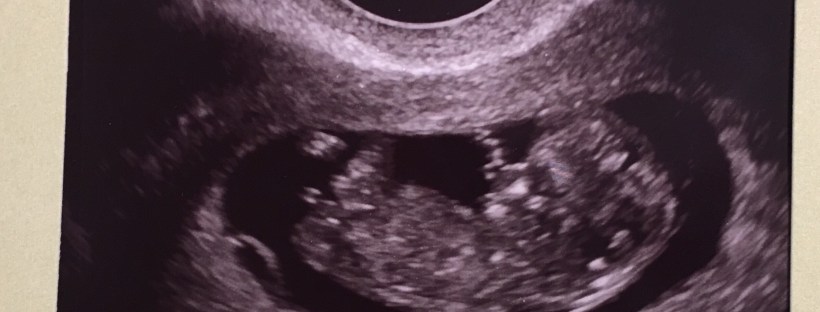

Anyways – On Friday, December 2nd, I went back for a dating ultrasound. During the first doctor’s appointment and ultrasound I had before Thanksgiving, Baby B was moving around a ton so they couldn’t measure how long he/she was. When I went back on what should have been my 11th week and 4th day of pregnancy – they were able to get a good measurement of Babes’ length and turns out… I was only 10 weeks and 4 days!

There’s an up and a down to not being as far along as they originally thought. The down – I have an additional week of nausea… yay! The up – they saw a tiny protrusion on the baby’s belly that typically continues to develop and goes away during week 11. Since I was only in the 10th week of pregnancy the baby has a whole extra week to cook and grow. I’m scheduled for another ultrasound this Friday, December 16th, to make sure the protrusion has gone away and our little nugget is still strong and healthy. We were able to see little nug and the heart beat is super strong which is awesome so the doctor doesn’t suspect there will be any issues.